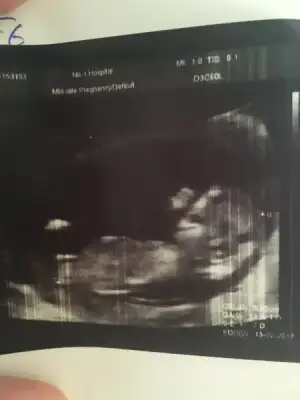

Slm kızlar hastaneden geliyorum. Kıpır kıpırdı sürekli el salladı minnak. Ense kalınlığı 1,3 çok iyi dedi doktor. 12 haftalık bugün tam ama 13+1 çıktı. Boyu 7cm olmuş. Fotosunu yükleyeyim bakalım cinsiyet için, doktor göstermiyor dedi sadece

Eklentiler

• image.webp

maşallah annesi yaaa.. sanki ağzı açık gülüyor gibi :nazar::KK51: